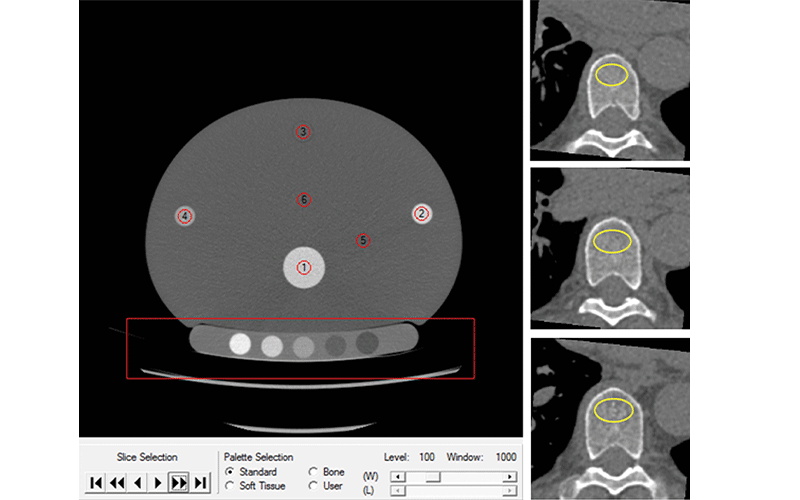

Dr. Therkildsen and colleagues recently looked at cardiac CT as an opportunistic way to screen for osteoporosis. Because the cardiac CT scan also visualizes the thoracic vertebrae, it is relatively easy to add a BMD test to the procedure.

The study involved 1,487 participants who underwent cardiac CT for evaluation of heart disease. Participants also had BMD testing of three thoracic vertebrae using quantitative CT software.

Adding BMD testing to cardiac CT is feasible and applicable in a clinical setting, according to Dr. Therkildsen. It does not add time to the exam and doesn’t expose the patient to any additional radiation. In fact, Dr. Therkildsen said, technological advances over time have reduced the radiation dose given at cardiac CT. BMD measurements can be made using existing non-enhanced CT images as long as a suitable calibration system is ensured, scanner stability is continuously monitored and systematic imaging acquisition techniques are implemented.